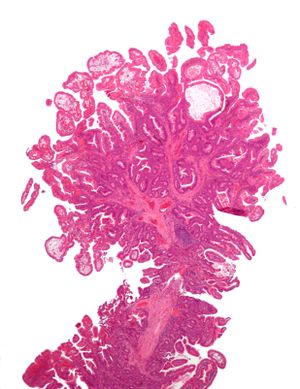

| Tubular Adenoma (Villous, Tubulovillous) | Tubular glands with elongated nuclei (at least low-grade atypia) | نعم | ||

- البوليبات الورمية: سليمة لكن قابلة للتسرطن, لها ثلاثة نماذج: أورام غدية انبوبية نسبتها 75% وأورام غدية زغابية نسبتها 10% وأورام غدية أنبوبية زغابية نسبتها 15%.

السلائل الغدية

الأنواع